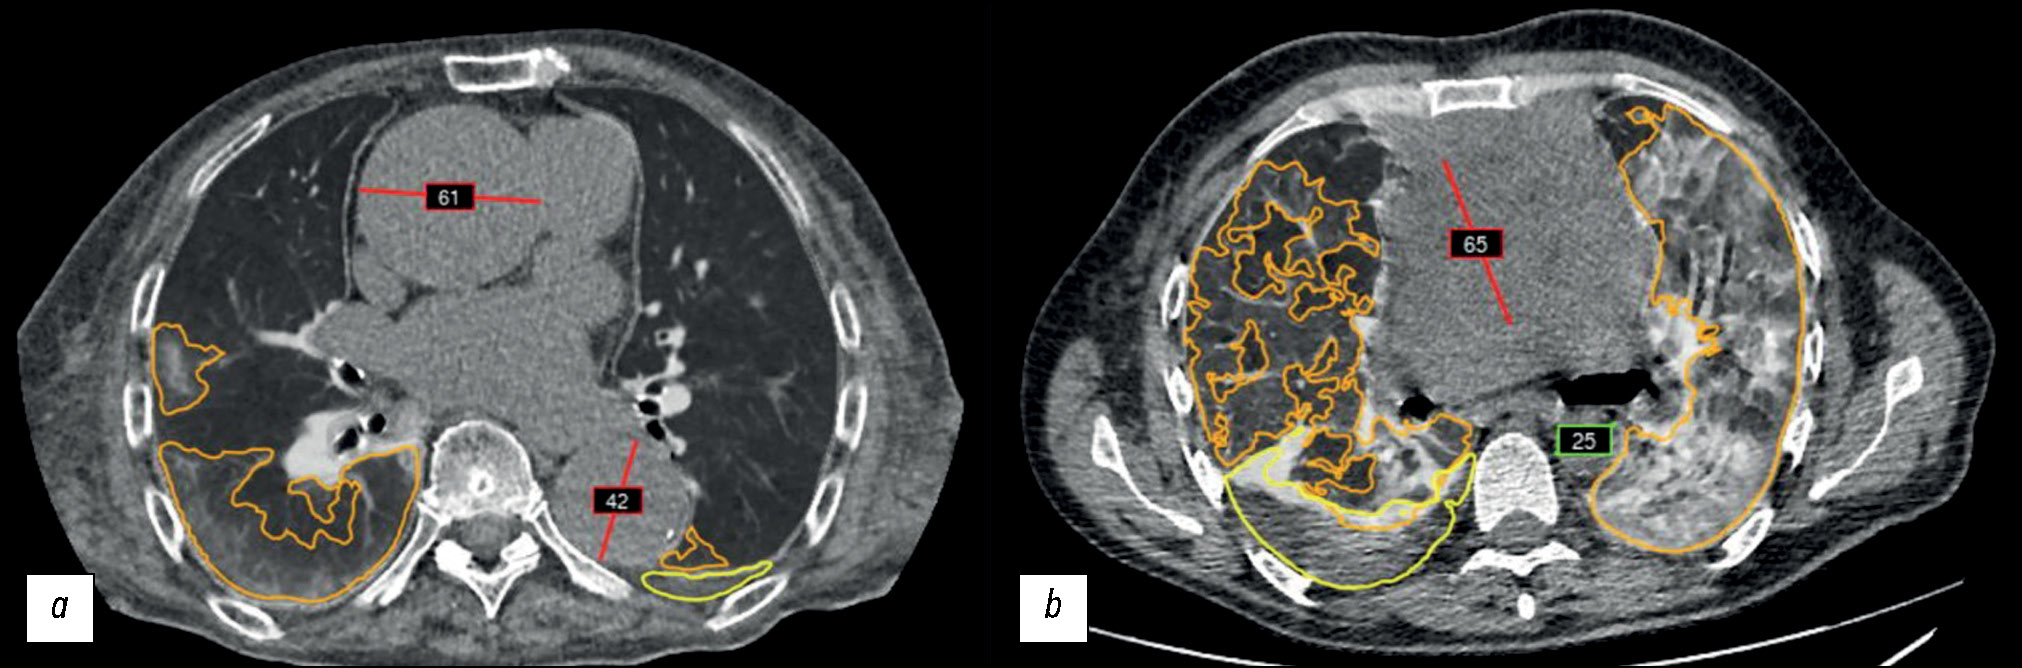

An example of an AI technology algorithm operation is presented in Fig. 2.

Fig. 2. An example of an algorithm operation of a complex AI-based service to process chest CT findings: a: AI technology correctly selected and marked (red line) the suspected ascending and descending thoracic aortic aneurysms; b: a false positive result: a mediastinal neoplasm was marked (red line) together with the ascending thoracic aorta; the green frame indicates the diameter of the descending thoracic aorta. This complex AI-based service has additional modules for marking pulmonary infiltrates (orange outline) and pleural effusion (yellow outline).

The AI technology algorithm was used to process 84,405 noncontrasted chest CT scans for detecting abnormal thoracic aortic dilatation. In total, 86 patients (62 male and 24 female patients) with a suspected thoracic aortic aneurysm according to AI technology findings were selected from this sample and retrospectively reviewed by radiologists and vascular surgeons. Of 86 patients, six were excluded from the sample because no protocol was available in the ERIS, and five had a false positive result after AI data processing (assessment of a nontarget pathology or organ, Fig. 2, b); these five patients were also excluded from the sample.